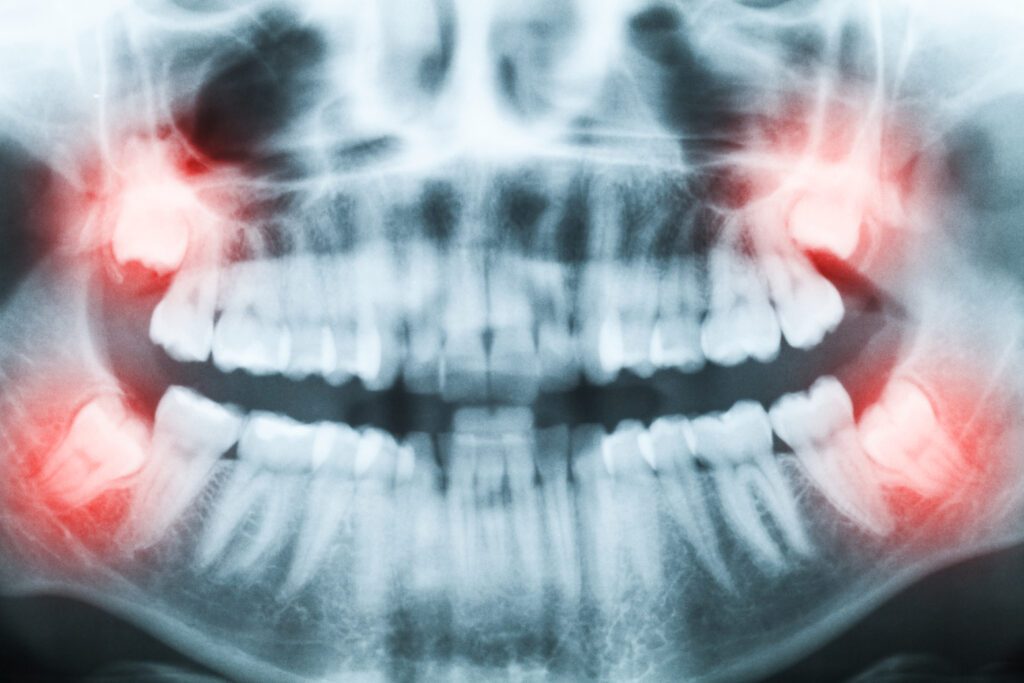

The specifics of installation surgery are dependent on where in the mouth the implant is added. Most single tooth implants are installed to replace a single back tooth. Premolars and molars are very often the first kind of teeth to be lost for two reasons: they experience the most wear because of their essential role in eating, and they are most susceptible to the effects of gum disease and decay.

Molars usually require a “two-phase” treatment sequence because they have at least two roots. When molars are replaced, any roots are first removed and then the bone is grafted (filled). A recovery of up to 12 weeks is common before the implant can be installed. Front teeth can also be replaced with dental implants. Because of the role of canine and incisor teeth in tearing food, installing an implant of the maximum size is good practice.